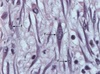

Macrófagos

Aspectos microscópicos?

Superfície irregular com protrusões e reentrâncias.

Mastócitos

Localização? (3)

- Derme;

- Trato digestivo;

- Trato respiratório.

Mastócitos

Aspectos microscópicos? (3)

- Célula globosa;

- Citoplasma ↑grânulos;

- Núcleo pequeno, esférico;